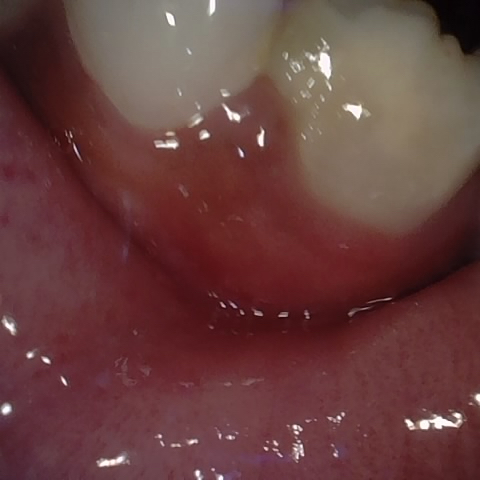

Annotated as "Bad"